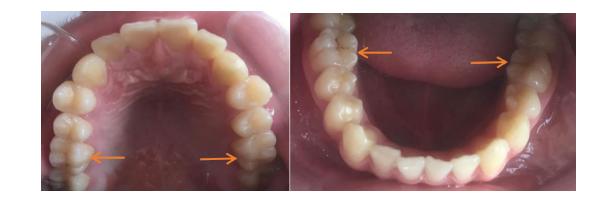

第一恒磨牙就是我们说的“六龄齿”,在儿童6岁左右萌出,上下左右各一颗(共4颗),即从中间往后数第六颗牙,此为恒牙,不再替换。

“六龄齿”非常重要,承担的咬合力和咀嚼功能比其他恒牙大。新萌出的“六龄齿”,窝沟点隙多,窝沟深,容易堆积食物残渣和菌斑,不容易清洁,易龋坏。

当“六龄齿”完全萌出,有深窝沟且未龋坏时,可以进行窝沟封闭。操作包括清洗牙面、酸蚀、冲洗和干燥、涂布封闭剂、固化、检查六个步骤。窝沟封闭操作时间短,在儿童配合时需5~10分钟。封闭用的材料对人体无毒、无害。